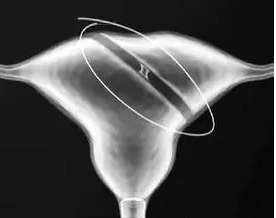

子宮縱隔到底是什么?得了子宮縱膈還能懷孕嗎?子宮縱隔是一種先天性子宮畸形,子宮縱隔尤其是完全性縱隔,一般對懷孕都會產生不同程度的影響。因此,如果檢查發現患有子宮縱隔的女性,及早治療是非常關鍵的。

子宮縱隔是先天發育中,雙副中腎管融合中受阻所致。子宮縱隔使子宮腔的對稱形態發生改變,干擾正常生育功能,引起原發性不孕或難治性不孕癥。